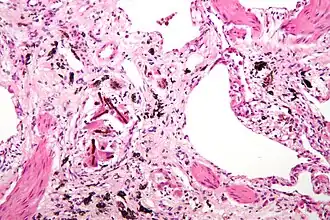

Micrografia de de asbestose (com corpos ferruginosos), um tipo de pneumoconiose. H&E stain.